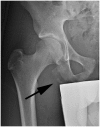

There is a continuum of hamstring injuries that can range from musculotendinous strains to avulsion injuries. Although the proximal hamstring complex has a strong bony attachment on the ischial tuberosity, hamstring injuries are common in athletic population and can affect all levels of athletes. Nonoperative treatment is mostly recommended in the setting of low-grade partial tears and insertional tendinosis. However, failure of nonoperative treatment of partial tears may benefit from surgical debridement and repair. The technique presented on this article allows for the endoscopic management of proximal hamstring tears and chronic ischial bursitis, which until now has been managed exclusively with much larger open approaches. The procedure allows for complete exposure of the posterior aspect of the hip in a safe, minimally invasive fashion.